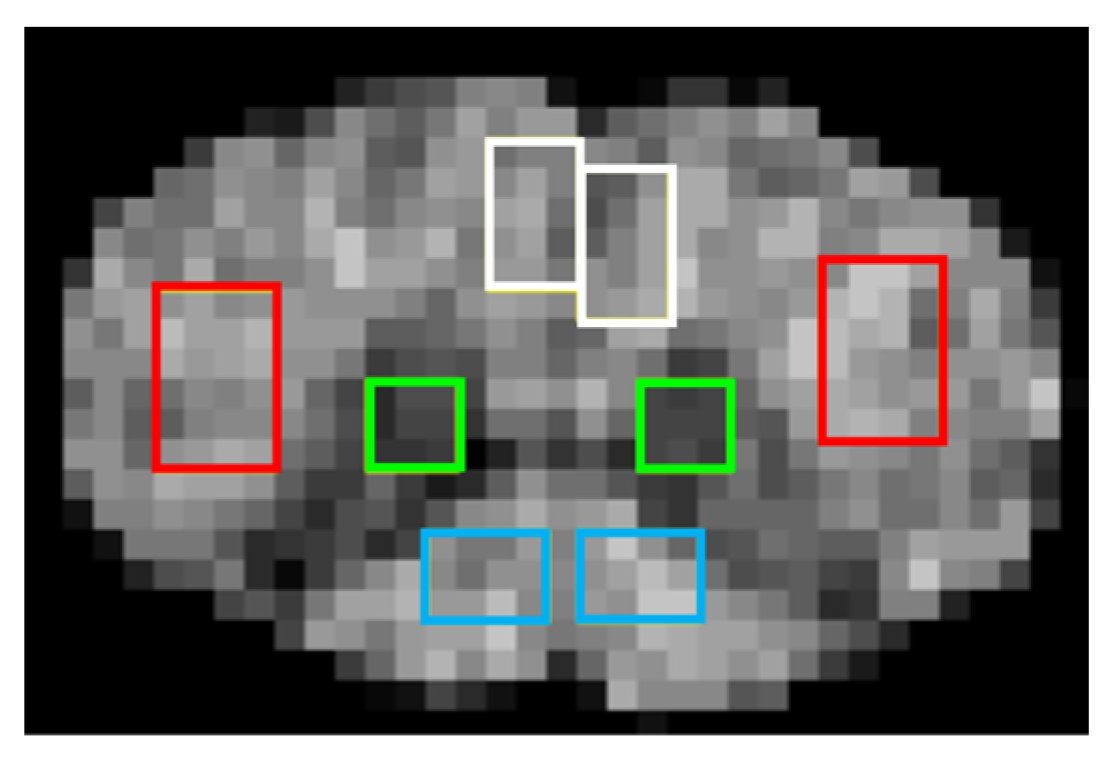

2.4. Measurement of Mean Values

3.1. Maps of Quantitative Indices

3.2. Histological Data